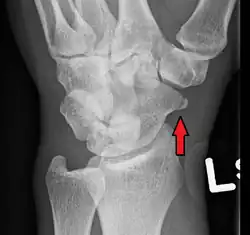

| An X-ray showing a fracture through the waist of the scaphoid | |

Scaphoid fractures are often diagnosed using plain radiographs and multiple views are obtained as standard.[9] However, not all fractures are apparent initially.[7] In 1/4 of cases, the clinical examination suggests a fracture, but the X-ray does not show it, even though there is indeed a fracture.[10] Therefore, people with tenderness over the scaphoid (those who exhibit pain to pressure in the anatomic snuff box) are often splinted in a thumb spica for 7–10 days at which point a second set of X-rays is taken.[7] If a minimally displaced fracture was present initially, healing will now be apparent. Even then a fracture may not be apparent. A CT Scan can then be used to evaluate the scaphoid with greater resolution. The use of MRI, if available, is preferred over CT and can give one an immediate diagnosis.[11] Bone scintigraphy is also an effective method for diagnosis fracture which do not appear on Xray.[12]

A subtle scaphoid fracture -

A more obvious scaphoid fracture on a scaphoid view X ray -

Radiolucency around a 12 days old scaphoid fracture that was initially barely visible.[13]